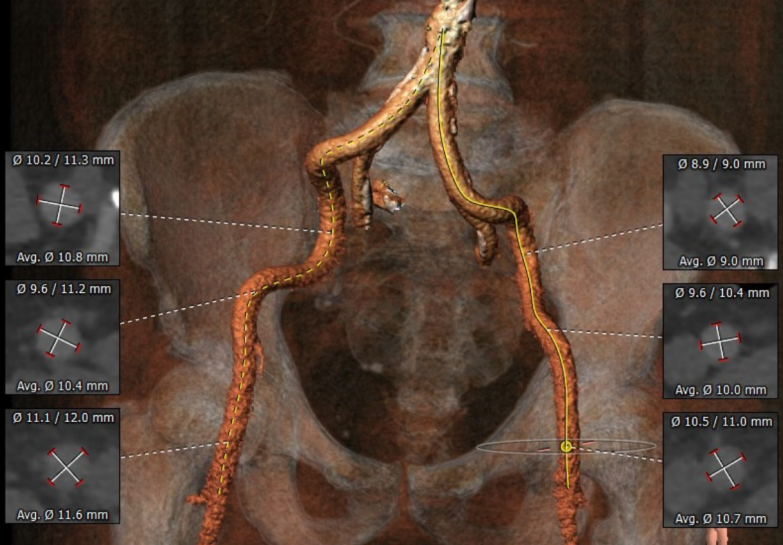

术前CT结果显示,患者主动脉瓣瓣环周长:67.4 mm,平均瓣环直径:21.5mm。左流出道平均直径20.9mm,瓦氏窦最小径31.7mm,窦管结合交界处(STJ)28.4mm,风湿性心脏病,三叶瓣,轻度钙化,瓣叶明显增厚,钙化,左冠开口高度12.2mm,右冠开口高度16.1mm,结合瓦氏窦内径,瓣叶长度及度钙化分布等综合因素考虑,冠脉风险较低,双侧入路血管直径尚可,无明显钙化,最小直径为5.5mm。

外周血管入路评估